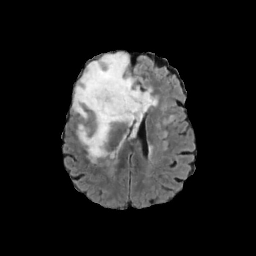

Refer to caption

(a) CT images.

(b) MRI images.

Figure 6: Lossy compression based attack on CT images (a) and MRI images (b) with a specific channel numbers (C8050\mathrm{C^{50}_{80}}) for the EP and IT Scenarios. StolenEPD1\mathrm{Stolen}^{\mathrm{D1}}_{\mathrm{EP}} denotes the decompressed images in the EP Scenario with a reduced D1 decoder.

Compression-Fidelity Compromise. Based on the previous results, we have selected the decoder D1D1 and the configuration of the latent and hyperlatent variables C8050\mathrm{C^{50}_{80}}, as the optimal architecture of the HiFiC encoder-decoder pair. In Fig. 6, we display more specifically the compression and reconstruction quality performances. In terms of reconstruction quality, we obtain a PSNR of approximately 40 for CT images and around 38 for MRI images while the MS_SSIM values are close to 1. This indicates an excellent perceptual quality of the reconstructed images that are hardly discernible from the original ones. In terms of compression efficiency, the Pratio\mathrm{P}_{\mathrm{ratio}} for CT images is approximately 0.015, indicating that the lossy image compression-based attack generated compressed images are 67 times smaller than those produced by the lossless zipped image compression-based attack. For MRI images, the Pratio\mathrm{P}_{\mathrm{ratio}} is around 0.12, 10 times higher than that of CT images, which can be attributed to the presence of a large uniform background in the skull-stripped original MR images.

A visual comparison between target and stolen images is available in Fig. 7. We observe that the stolen images from IT Scenario closely resemble the input ones, particularly in the tumor regions, whereas stolen images from EP Scenario exhibit blurring artifacts in finer details. In both cases, the stolen images reconstructed by D1D1 demonstrate a comparable quality to those reconstructed by DD, thus further confirming the effectiveness of the reduced decoder D1D1.